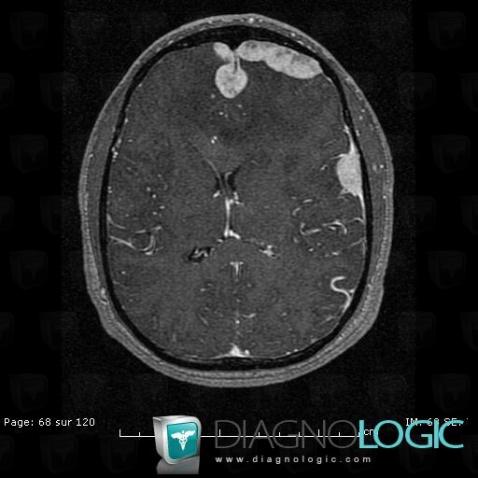

Langerhans cell histiocytosis, Cerebral hemispheres, MRI

Here is the specific information in the key image above:

- Diagnosis Langerhans cell histiocytosis, Location(s) Cerebral hemispheres, with gamuts Multifocal intracranial lesions